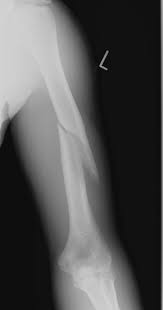

6.  Your patient is a 24 year old male that presents with the following x ray below. Which of the following nerve injuries have been associated with this type of injury?

A.  Median Nerve

B.  Ulnar Nerve

C.  Axillary Nerve

D.  Radial Nerve